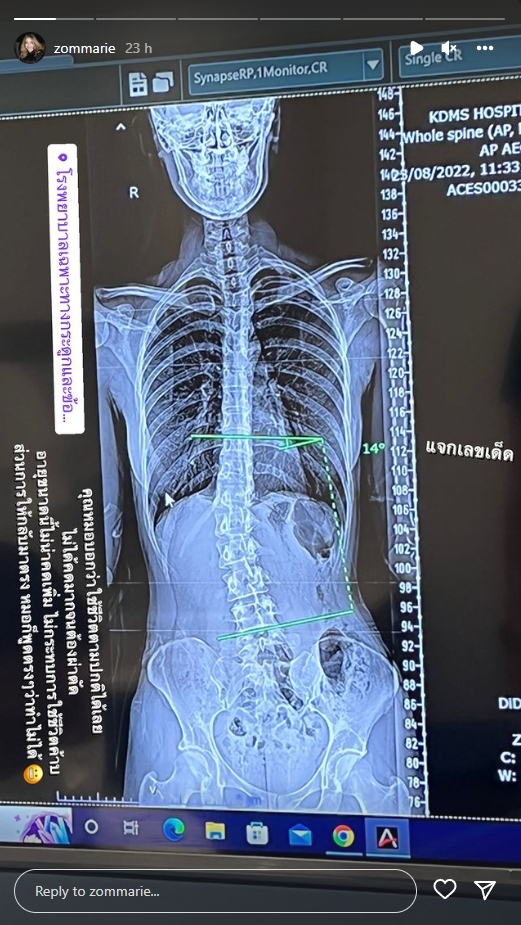

ภาพเอ็กซเรย์กระดูกสันหลังเผยให้เห็นกระดูดคด อย่างชัดเจนลงอินสตาแกรมส่วนตัว

“เคล็ดลับเอวเอส.. วัยรุ่นกระดูกคด จริงๆ รู้ตัวมาหลายปีแล้วว่ากระดูกสันหลังคด เคยตรวจมาก่อน คุณหมอก็บอกว่าไม่ได้ต้องทำอะไร วันนี้ลองมาตรวจอีกสักที สรุปก็คล้ายเดิมฮะ คุณหมอบอกว่า 14 องศาไม่ได้อันตราย และด้วยอายุขนาดนี้ไม่น่าคดเพิ่มแล้ว คุณหมอบอกว่าไม่ต้องทำอะไรค่ะ ใช้ชีวิตไปปกติได้เลย ออกกำลังกายสม่ำเสมอเพื่อให้กล้ามเนื้อแข็งแรง การจะทำให้มันกลับมาตรง คือทำไม่ได้นะคะ เพราะร่างกายเราปรับไปกับโครงสร้างของเราแบบนี้ไปแล้ว และการจัดกระดูกไม่ช่วยอะไรค้าบ”

นอกจากนี้ ส้ม ยังได้อัพเดตผ่านทางไอจีสตอรี่อีกว่า… “คุณหมอบอกว่าใช้ชีวิตตามปกติได้เลย ไม่ได้คดมากจนต้องผ่าตัด อายุขนาดนี้ไม่น่าคดเพิ่ม ไม่กระทบการใช้ชีวิต ส่วนการให้กลับมาตรง หมอก็พูดตรงๆ ว่าทำไม่ได้”